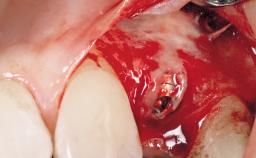

Immediate Flapless Placement of an Implant in a Maxillary Right Lateral Incisor Site

This 43-year-old male patient, a non-smoker, came to our practice because of a fracture of tooth 12 caused by a bicycle accident. Due to the combined para- and infrabony crown and root fracture, tooth extraction, and subsequent implant placement were suggested to the patient as the therapy of choice. The patient had high esthetic expectations with regard to the treatment outcome and asked for an immediate fixed provisional restoration. His individual esthetic risk profile summed up to a medium esthetic risk.

Placement Protocol Immediate implant placement

Tooth Site Maxillary incisor or canine

Socket Morphology Single-root socket

Socket Integrity Sufficient, with intact bone walls